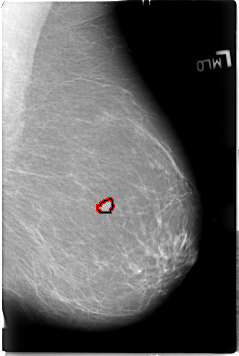

B_3018_1.LEFT_MLO

FILE: B_3018_1.LEFT_MLO.OVERLAY

TOTAL_ABNORMALITIES 1

ABNORMALITY 1

LESION_TYPE MASS SHAPE LOBULATED MARGINS ILL_DEFINED

ASSESSMENT 4

SUBTLETY 4

PATHOLOGY MALIGNANT

TOTAL_OUTLINES 1

BOUNDARY